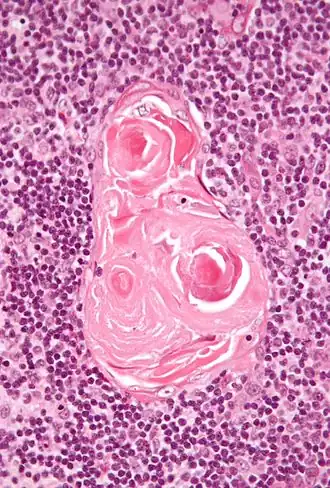

Micrograph of a thymic corpuscle; H&E stain. | |

Hassall's corpuscles (also known as thymic bodies) are structures found in the medulla of the human thymus, formed from eosinophilic type VI thymic epithelial cells arranged concentrically. These concentric corpuscles are composed of a central mass, consisting of one or more granular cells, and of a capsule formed of epithelioid cells. They vary in size with diameters from 20 to more than 100 μm, and tend to grow larger with age.[1] They can be spherical or ovoid and their epithelial cells contain keratohyalin and bundles of cytoplasmic fibres.[2] Later studies indicate that Hassall's corpuscles differentiate from medullary thymic epithelial cells after they lose autoimmune regulator (AIRE) expression.[3] This makes them an example of Thymic mimetic cells.[4] They are named for Arthur Hill Hassall, who discovered them in 1846.[5][6]